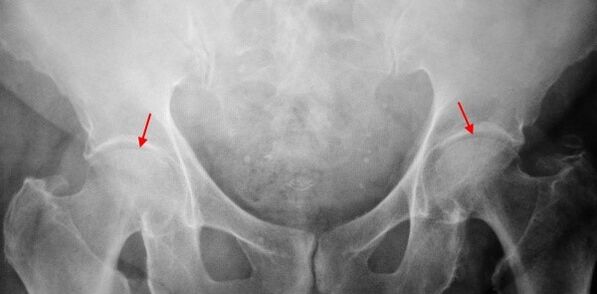

On the X -ray of the patient with 1st degree coxarthrosis, light changes are determined: moderate unequal narrowing of the joint difference, as well as bone growth around the external or internal acetabulum edge in the absence of changes in the head of the femur.

In x -ray images for 2nd degree coxarthrosis, a significant unequal narrowing of the joint deviation (more than half of the normal height) is determined.The femoral head is somewhat offset upwards, distorted and increased in size, and its contours become uneven.Bone growth with this degree of coxarthrosis appear not only on the interns, but also on the outer edge of the acetabulum and get out of the cartilage.

On 3rd degree coxarthrosis radiographs, a net narrowing of the joint gap, a pronounced expansion of the thigh head and multiple bone growths are detected.

The diagnosis of coxarthrosis is based on clinical signs and additional study data, the main one of which is radiography.In many cases, X -rays make it possible to establish not only the degree of coxarthrosis, but also the cause of its occurrence.Thus, for example, an increase in the angle of the coueticphysian, the scenes and the flattening of the acetabulum indicate dysplasia, and the changes in the form of the proximal part of the femur are indicated that coksartrose is a consequence of the disease of losses or young epiphysiolysis.On patients with patients with coxarthrosis, changes can also be detected indicating injuries.